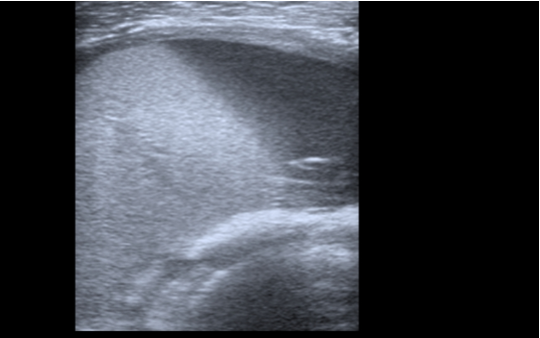

Hematoma no encapsulado de 5 x 9 cm en vasto intermedio, sin captación de doppler color y con aparición en bordes externos de calcificaciones con sombra acústica posterior.

Bajo correctas medidas de asepsia con clorhexidina al 2%, y mediante aguja espinal de 20G, se realiza drenaje completo del hematoma, vendaje compresivo y nueva derivación a fisioterapia para continuar con tratamiento.